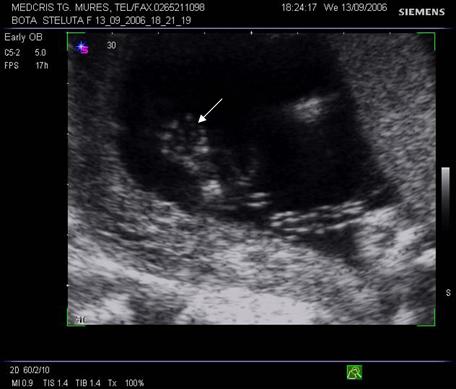

Fig nr. 8. Sarcina 5 sapt la ecografia transvaginala :sac ovular cu vezicula vitelina evidenta marcata cu sageata, retrouterin ovar chistic

Fig nr.9. Vezicula vitelina, marcata cu sageata, la ecografia transvaginala, sarcina 5 sapt.